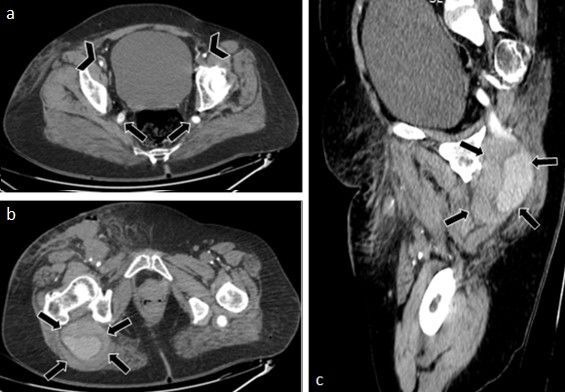

Persistent sciatic artery is a rare congenital anomaly, with few cases described in the literature. This study presents a case of this embryological variation observed in a patient's lower limb circulatory system. The anatomical description is based on a review of medical records and imaging exams. This case report describes a 63-year-old female patient admitted to the emergency department complaining of severe pain in the right lower limb, with a cold, pale extremity and ecchymosis on the dorsum of the foot. Duplex ultrasound showed no detectable flow in the anterior tibial and fibular arteries and a tardus parvus pattern in the posterior tibial artery. The patient developed loss of movement and fixed cyanosis in the right foot and was referred for urgent thromboembolectomy. However, adequate reperfusion was not seen after the procedure. Angiotomography was performed on the first postoperative day, showing bilateral persistence of the sciatic artery, with aneurysmal degeneration, partially thrombosed, and no opacification of the arterial system downstream of the aneurysm. By the third postoperative day, the patient had developed areas of dry necrosis in the limb, with no perfusion to the ankle, and underwent transfemoral amputation. Despite being a rare condition, it is of great clinical importance because of the high complication rates.